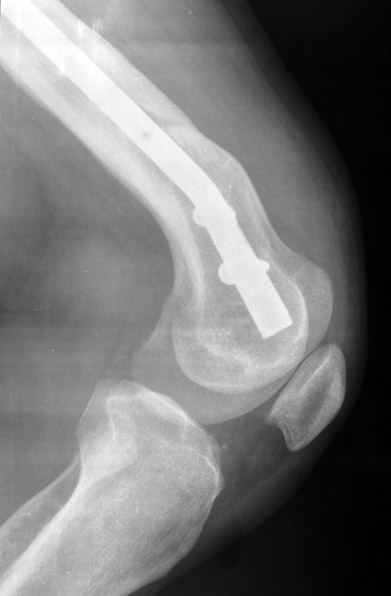

Bu Bacak Kısalık tipi bir kırığın kısalmış pozisyonda kaynaması ile oluşur. Bir çok vaka yetişkinlerde görülür ve sadece bir uzatma ile tedavi edilebilir. Ek deformiteler de aynı anda düzeltilebilir. Bu hastaların çoğu çivi üzerinden uzatma veya tam implante edilen çivi ile tedavi edilebilirler.